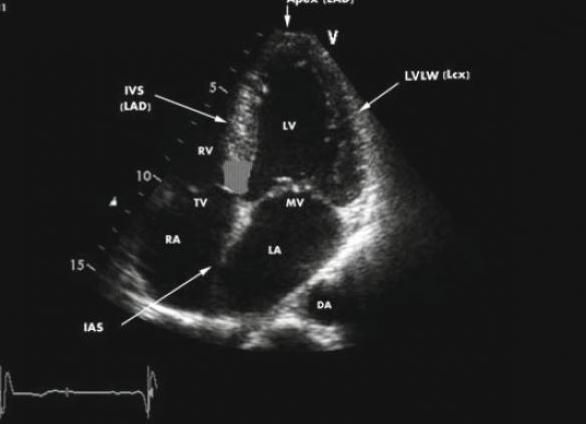

С помощью эхокардиографии исследуют клапаны, сердечную мышцу, желудочки, сосуды. Изучают скорость и направление движений кровяных потоков. Если возникли какие-либо патологии, врач это сразу увидит на экране монитора.

Диагностика помогает контролировать изменения работы сердца и сосудов. Благодаря процедуре есть возможность получения изображений сердца в разных плоскостях, по которым делают вывод о функциональности и структуре. С помощью УЗИ можно оценить состояние:

- Клапанов. Диагностирование помогает изучить развитие отклонений и вовремя прооперировать пациента.

- Камер – размер стенок, сократимость миокарда.

- Крупных сосудов.